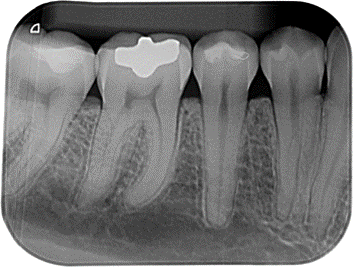

PERIAPICAL

Permite ver las zonas de interés con mayor definición y detalle, permite establecer una relación con estructuras adyacentes anatómicas o patológicas.

la serie periapical, es un estudio completo de los dientes y de sus estructuras mas cercanas.